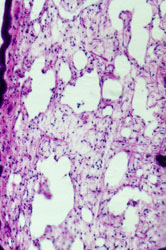

Gałąź medycyny zajmująca się regeneracją tkanek oferuje nowe możliwości w zakresie regeneracji funkcjonalnej i strukturalnej uszkodzonych tkanek. Jedno z podejść obejmuje umieszczanie komórek na szkielecie trójwymiarowym, na którym komórki mogą się osadzać i rosnąć. Dodanie czynników wzrostu usprawnia wzrost i różnicowanie się komórek na szkielecie. Szkielety magnetyczne wyróżniają się wyjątkowymi właściwościami, których nie zapewniają inne metody oraz materiały. Dają one również możliwość kontrolowanego uwalniania lub zmiennego dawkowania czynników wzrostu, stymulacji mechanicznej osadzonych komórek oraz konstruowania żądanej konfiguracji szkieletu. Fundusze na realizację 4-letniego projektu 'Magnetic scaffolds for in vivo tissue engineering' (MAGISTER) zapewniła UE. W ramach projektu pomyślnie opracowano innowacyjne, praktyczne zastosowania szkieletów magnetycznych w dziedzinie inżynierii tkankowej I regeneracji tkanek. Badacze opracowali I uzyskali wiele biokompatybilnych materiałów magnetycznych do tworzenia szkieletów. Polimery hydroksyapatytowe, żelatynowe I koralowe zaimpregnowano nanocząsteczkami magnetycznymi opracowanymi przez konsorcjum projektu lub dostępnymi już na rynku. Wykorzystanie połączenia kwasów humusowych I magnetytu doprowadziło do powstania nowych, w pełni bioresorbowalnych I biokompatybilnych materiałów. Opracowano także nowe agregaty czynników biologicznych I nanocząsteczek magnetycznych (BIOAG), umożliwiające kontrolowane doprowadzanie zarówno czynników wzrostu śródbłonka naczyniowego, jak I komórek macierzystych. W tej technologii połączono wytwarzanie nanocząsteczek magnetycznych z innowacyjną metodą funkcjonalizacji powierzchni, opartą na zastosowaniu innowacyjnych biokompetentnych peptydów wielorozgałęzionych (dendronów). Dendrony opracowano tak, by funkcjonalizowały powierzchnię nanocząsteczek magnetycznych oraz kontrolowały ekspozycję grup funkcyjnych zdolnych do wiązania czynników wzrostu śródbłonka naczyniowego. Podejście to umożliwiło usprawnienie angiogenezy poprzez ograniczenie namagnetyzowania komórek macierzystych oraz komórek śródbłonka. Na modelu in vitro badacze zaprezentowali wyraźną równoczesną, magnetycznie naprowadzaną kolonizację włókien szkieletu przez dwa różne typy komórek. Wyniki in vivo wykazały również, że magnetyczne naprowadzanie czynników biologicznych wewnątrz szkieletów magnetycznych zapewnia znakomite efekty rekonstrukcji tkanek z wyraźnym unaczynieniem. Wyniki projektu zaprezentowano w 14 publikacjach. Prace prowadzone w ramach projektu MAGISTER oznaczają, że szkielety magnetyczne mogą być używane jako elementy zapewniające długotrwałe wspomaganie w inżynierii tkankowej. Zapewnia to wyjątkowe możliwości w zakresie dostosowywania funkcjonowania szkieletów do indywidualnych potrzeb pacjentów.